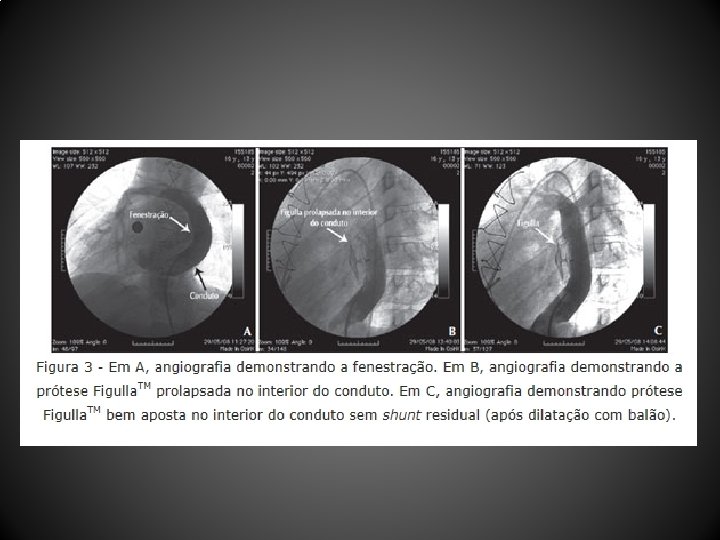

Resultados • Entre abril de 2004 e dezembro de 2010, 12 pacientes (média de idade, 103, 1 + 88, 6 meses; peso, 29, 9 + 12, 7 kg) submetidos a CF (10 tubos extracardíacos, 2 túneis intra-atriais) foram tratados 44, 1 + 26, 7 meses após a CF • Um paciente não tolerou o teste de oclusão com o balão, sendo contraindicado o procedimento • As próteses utilizadas foram: Helex. TM (4 pacientes), Amplatzer. TM (2 pacientes), Cardia Atriasept. TM (2 pacientes), Figulla. TM (1 paciente), Cera. TM (1 paciente), e 1 stent coberto Cheatham-Platinum. TM • Após a oclusão da fenestração, a saturação de oxigênio aumentou significativamente (82, 1 + 6, 5% para 95, 2 + 3, 2%), sem aumento significativo da pressão venosa central (12, 4 + 2, 6 mm. Hg para 14, 5 + 2, 3 mm. Hg) nem queda do débito cardíaco • Após o procedimento foi observado shunt residual imediato em 5 pacientes, que desapareceu antes da alta